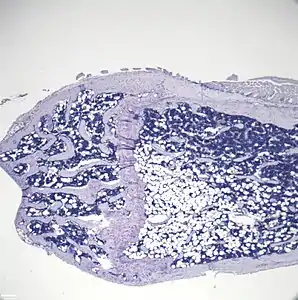

- Histologic sections demonstrating Marrow Adipocytes

Representative distal femur histologic section of a 16-week-old healthy C57BL/6 mouse demonstrating a typical quantity of marrow adipocytes.

Representative distal femur histologic section of a 16-week-old C57BL/6 mouse after 6 weeks of calorie restriction demonstrating an increased quantity of marrow adipocytes.